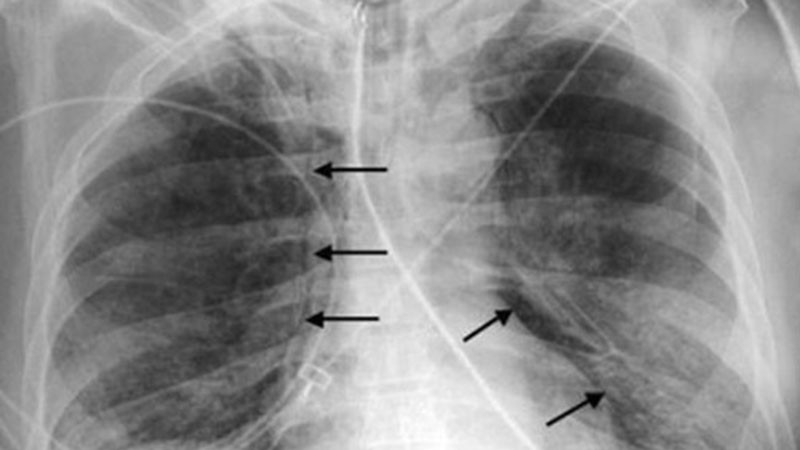

Установен е първи случай на ку-треска в Пловдив тази година. Засегнат е 67-годишен мъж, хоспитализиран с двойна бронхопневмония на 6 април, пише "Фокус". Близо седмица по-късно мъжът е изписан.

Инфекцията е резултат от вдишване на споровиден дребноклетъчен вариант и от контакт с млякото, урината, изпражненията и секрети на заразени животни. Рядко заболяването се пренася от кърлежи. Инкубационният период е 9-40 дни. Хората са уязвими на заболяването и инфекцията може да бъде резултат от дори няколко организма.